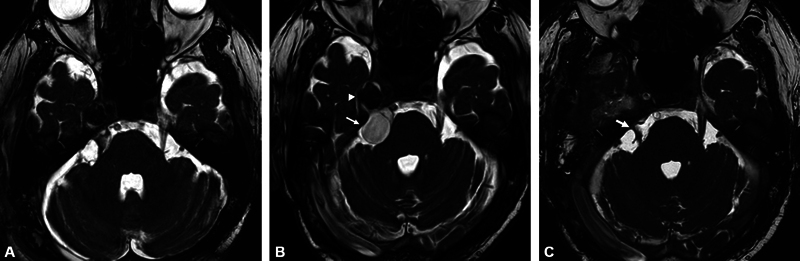

神经轴钙化假性肿瘤(CAPNON)是罕见的非肿瘤性钙化病变,可发生在整个神经轴。颅底病变可累及脑神经。手术切除通常预后良好,相关文献仅报道少数复发病例。我们经历了一例Meckel's cave的CAPNON复发病例,在最初切除病变的囊性部分后,CAPNON延伸到桥小脑池并累及三叉神经。48岁男性,右侧上睑下垂4年。磁共振成像显示在Meckel洞内出现钙化病变,伴囊性病变延伸至桥脑小脑池。病变的囊性部分在初始手术中使用右侧枕下外侧入路切除。然而,囊性病变在23个月内恢复到术前大小。在切除过程中,采用右侧硬膜外颞下入路成功切除右侧Meckel腔内钙化肿块和延伸至右侧桥小脑池的囊性病变。术后患者神经系统症状消失。组织病理学检查发现CAPNON。本报告描述一例罕见的Meckel洞穴CAPNON病例,具有独特的临床病程。第一次手术后,桥小脑池囊性病变复发,但第二次手术成功治疗。

Calcifying pseudoneoplasms of the neuraxis (CAPNON) are rare non-neoplastic calcified lesions that can occur throughout the entire neuraxis. Cranial nerves may be involved in skull base lesions. Surgical resection usually has a good prognosis, with only a few cases of recurrence reported in the relevant literature. We experienced a recurrent case of CAPNON in Meckel's cave extending to the cerebellopontine cistern with involvement of the trigeminal nerve after initial resection of the cystic part of the lesion. A 48-year-old man presented with a 4-year history of right-sided ptosis. Magnetic resonance imaging revealed a calcified lesion arising in Meckel's cave, with a cystic lesion extending to the cerebellopontine cistern. The cystic part of the lesion was excised during the initial surgery using the right lateral suboccipital approach. However, the cystic lesion regrew to its preoperative size within 23 months. The right extradural subtemporal approach was used to successfully remove both the calcified mass in the right Meckel cave and the cystic lesion extending to the right cerebellopontine cistern during the resection of the lesion. The patient's neurological symptoms resolved postoperatively. CAPNON was identified during the histopathological examination. This report describes a rare case of CAPNON in Meckel's cave with a unique clinical course. After the first operation, cystic lesions recurred in the cerebellopontine cistern, but they were successfully treated by a second operation.